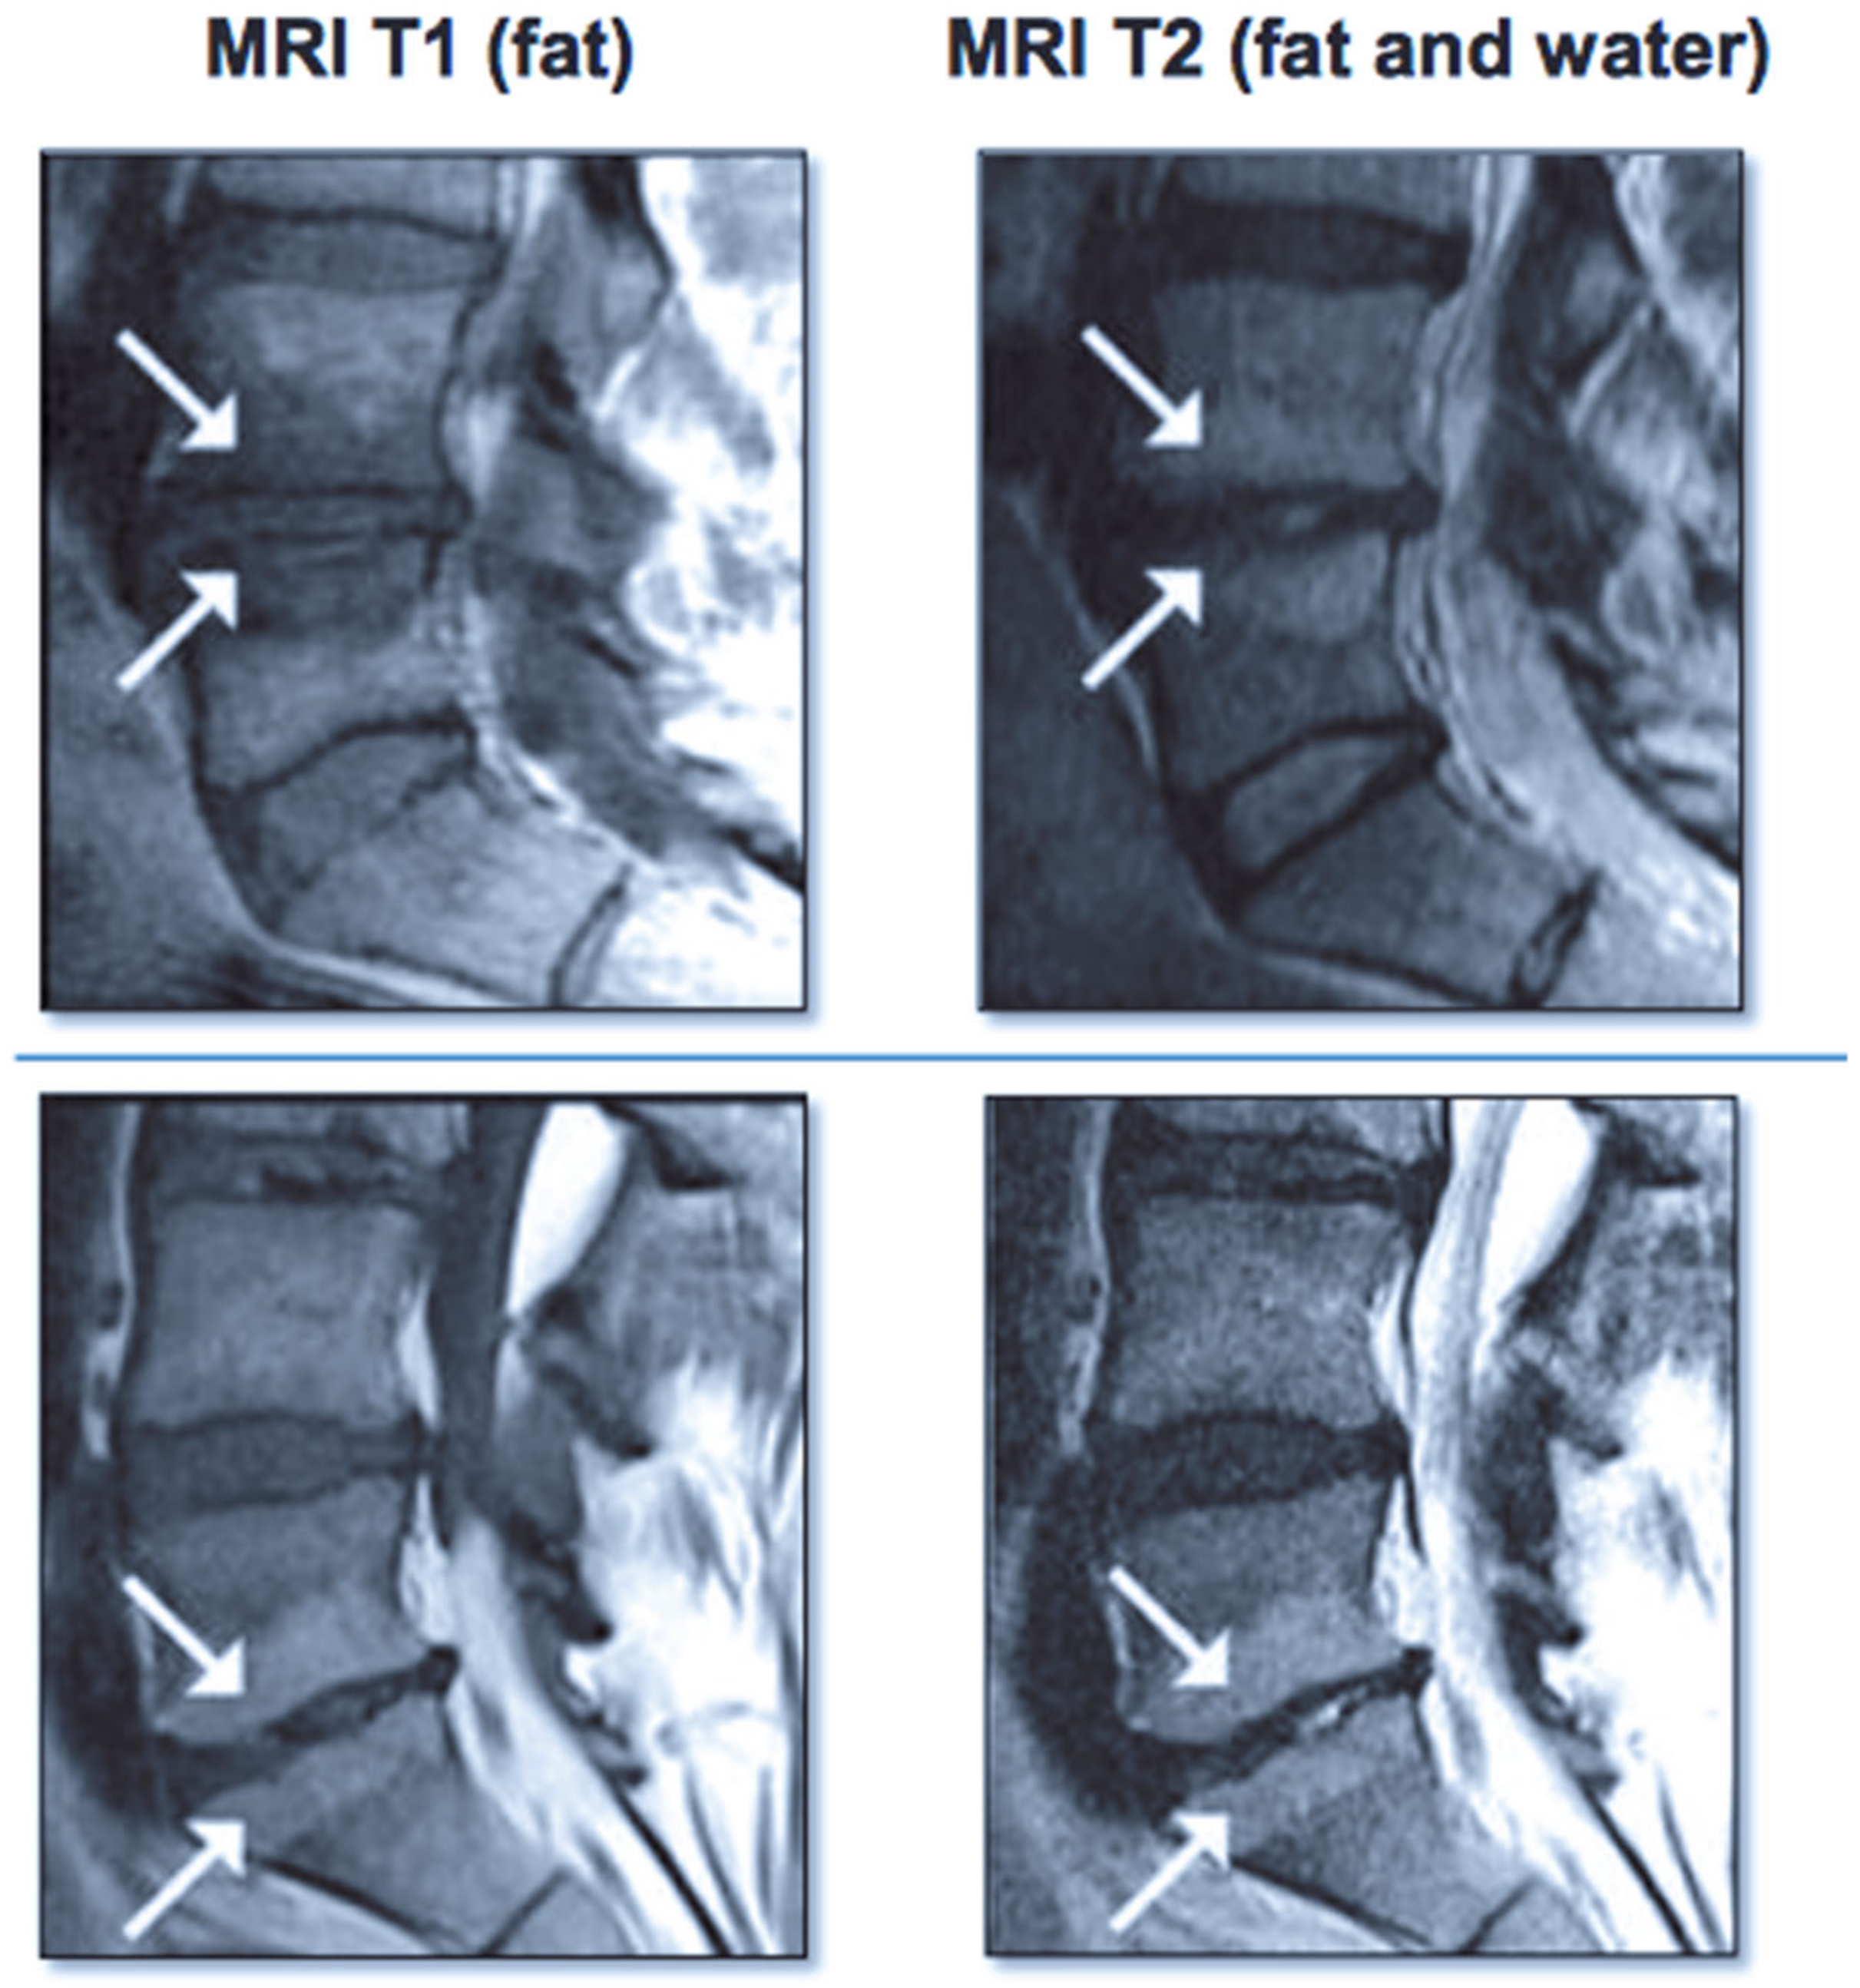

- Modic, M.T.; Steinberg, P.M.; Ross, J.S.; Masaryk, T.J.; Carter, J.R. Degenerative disk disease: Assessment of changes in vertebral body marrow with MR imaging. Radiology 1988, 166, 193–199. [Google Scholar] [CrossRef]

- Jensen, T.S.; Karppinen, J.; Sorensen, J.S.; Niinimäki, J.; Leboeuf-Yde, C. Vertebral endplate signal changes (Modic change): A systematic literature review of prevalence and association with non-specific low back pain. Eur. Spine J. 2008, 17, 1407–1422. [Google Scholar] [CrossRef] [PubMed] [Green Version]

- Herlin, C.; Kjaer, P.; Espeland, A.; Skouen, J.S.; Leboeuf-Yde, C.; Karppinen, J.; Niinimaki, J.; Sorensen, J.S.; Storheim, K.; Jensen, T.S. Modic changes—Their associations with low back pain and activity limitation: A systematic literature review and meta-analysis. PLoS ONE 2018, 13, e0200677. [Google Scholar] [CrossRef]

- Mera, Y.; Teraguchi, M.; Hashizume, H.; Oka, H.; Muraki, S.; Akune, T.; Kawaguchi, H.; Nakamura, K.; Tamai, H.; Tanaka, S.; et al. Association between types of Modic changes in the lumbar region and low back pain in a large cohort: The Wakayama spine study. Eur. Spine J. 2021, 30, 1011–1017. [Google Scholar] [CrossRef]

- Applebaum, A.; Nessim, A.; Cho, W. Modic Change: An emerging complication in the aging population. Clin. Spine Surg. 2021. [Google Scholar] [CrossRef]